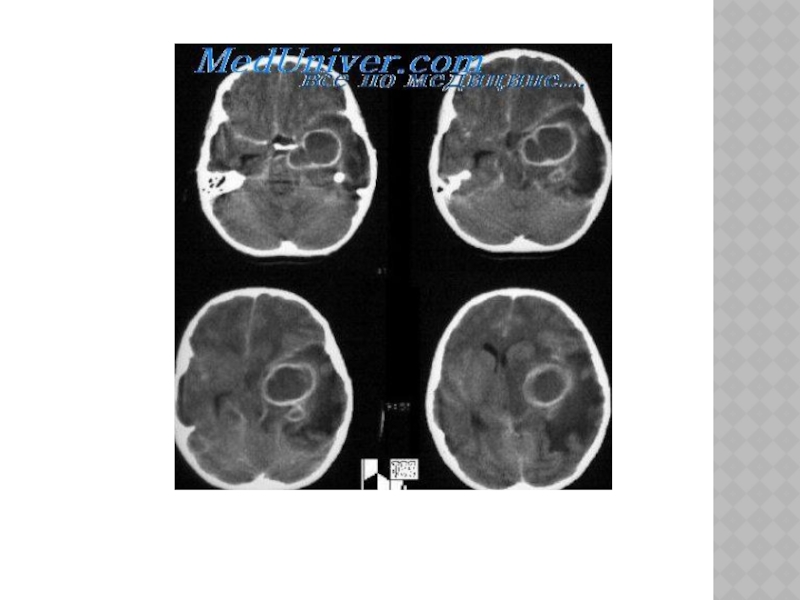

Слайд 113ОПУХОЛИ ГОЛОВНОГО МОЗГА

Классификация:

1) от вида ткани, из которой они растут,- менингеомы,

арахноэндотелиомы, глиомы, астроцитомы и т.д.;

2) от локализации - внемозговые, внутримозговые, больших полушарий, мозжечка, ствола, гипофиза и др.

3) от доброкачественности - доброкачественные, злокачественные;

4) от расположения по отношению к намету мозжечка (супратенториальные - расположенные над наметом, субтенториальные);

5) от локализации основного очага - первичные, растущие из тканей мозга, и метастатические, занесенные из других систем организма.

Доброкачественными считаются ограниченные опухоли с медленным ростом, злокачественными - опухоли, обладающие

инфильтративным ростом.

Опухоли составляют 4,5% всех органических заболеваний головного мозга и встречаются преимущественно в возрасте 20-40 лет.

Слайд 115КЛИНИКА

-симптомы зависят от локализации опухоли.

-при опухолях полушарий -очаговые симптомы, общемозговые.

-при опухолях ствола, мозжечка на первый план выступают общемозговые симптомы, что обусловлено ограниченным пространством задней черепной ямки, сдавлением ликворопроводящих путей.

-при опухолях гипофиза ранними признаками являются нарушения эндокринных функций (расстройство менструального цикла, ожирение, усиленный рост пальцев рук, ног и т.д.).

-при опухолях затылочной доли -расстройства зрения (зрительная агнозия, скотомы, зрительные галлюцинации).

-при поражении височной доли -обонятельные, вкусовые галлюцинации, расстройство памяти, психомоторные пароксизмы.

-опухоли лобной доли -моторные и эпилептические пароксизмы, парезы, расстройства речи, «лобная психика» (слабодушие, неряшливость, пассивность, ограничение круга интересов).

-опухоли мозжечка –нарушение походки(«пьяная походка»), координации произвольных и непроизвольных движений (нистагм, промахивание и интенционный тремор при выполнении пальценосовой, колено- пяточной проб и др.).

Слайд 117ДИАГНОСТИКА

Электроэнцефалография, эхоэнцефалоскопия, рентгенография черепа, ангиография, компьютерная рентгеновская и магниторезонансная томография, офтальмологическое

обследование.

Слайд 122ЛЕЧЕНИЕ

-хирургическое вмешательство

-симптоматическая терапия- дегидратационные средства, анальгетики, противосудорожные препараты (финлепсин, корбамазепин, соли

вальпроевой кислотыи др.) - при опухолях гипофиза -рентгенотерапия(эпендиома, медуллобластома, герминома, аденома гипофиза) -химиотерапия- прокарбазин, ломустин, винкристин (глиомы, астроцитомы), при пинеобластомах, медуллобластомах, герминомах наряду с радиотерапией используются производные платины (цисnлатин, карбоплатин), этопозид, блеоиин.